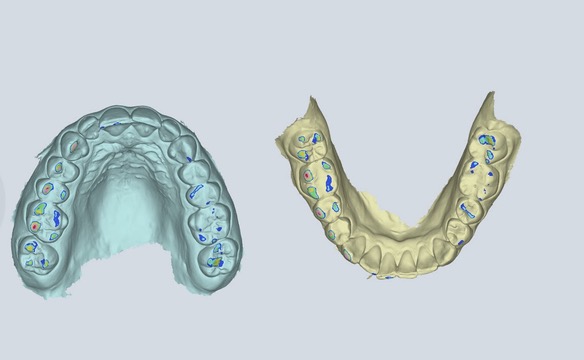

Mit unserer digitalen Funktionsanalyse erfassen wir Ihre Kieferfunktion in 4D-Bewegung, um Behandlungen zu entwickeln, die sich genauso gut anfühlen wie sie aussehen. Schnell und strahlungsfrei – für detaillierte Einblicke in Biss, Kiefergelenke und Kaufunktion in Echtzeit und in Zeitlupe.

Sehen Sie genau, wie sich Ihr Unterkiefer in Echtzeit bewegt – und Probleme entdecken, die statische Messungen übersehen.

Wir beginnen mit einer digitalen 4D-Funktionsdiagnostik, um zu erfassen, wie sich Ihr Kiefer in Echtzeit bewegt. Schnell, berührungslos und strahlungsfrei – für einen vollständigen Blick auf Biss, Gelenke und Funktion. Kein Rätselraten. Nur Klarheit.

Jedes Lächeln erzählt eine Geschichte – und Ihr Kiefer auch. Mit unserer digitalen 4D-Diagnostik sehen Sie, wie Ihr gesamter Kauapparat funktioniert, bevor wir starten – und was wir verbessern sollten.

Mit Modjaw® sehen wir Ihren Kiefer in Bewegung – beim Kauen, Sprechen und Zubeißen. Das bedeutet mehr Informationen und von Anfang an eine präzisere, individuellere Behandlung.